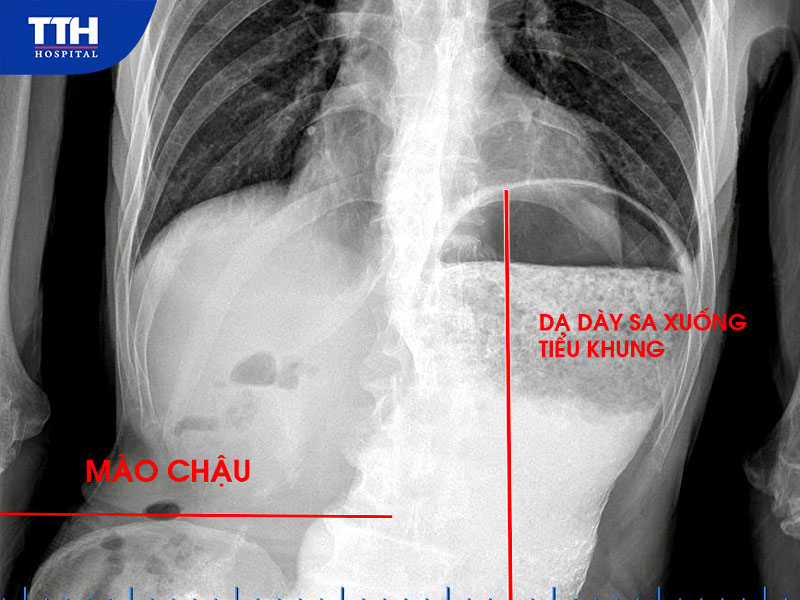

•    Chụp dạ dày cản quang ghi nhận dạ dày giãn lớn, sa thấp xuống dưới mào chậu, kéo dài đến tiểu khung